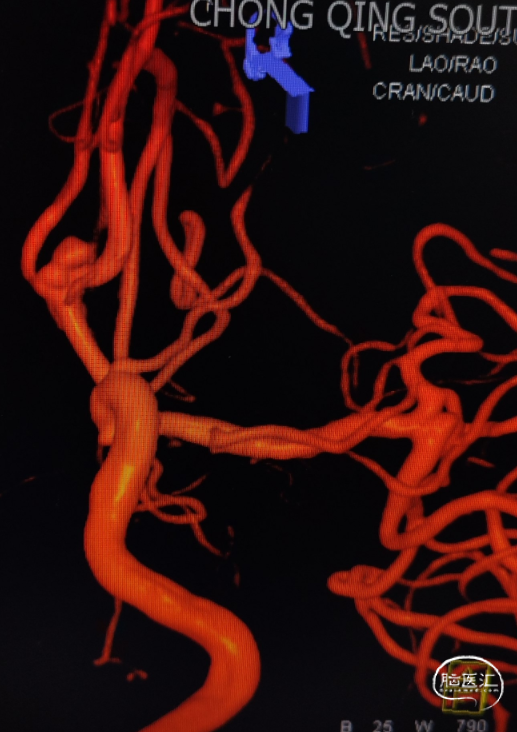

完善头颅CTA显示:前交通动脉瘤、左侧大脑中M1段末端动脉瘤。

DSA造影确认前交通动脉瘤、左侧大脑中M1段分叉部动脉瘤。

前交通动脉瘤5.94mm*4.12mm,瘤体呈分叶状。

患者右侧大脑前发育纤细;后循环血管无明显异常。

①以Seldinger技术经右侧股动脉穿刺,造影后选取工作位并建立路径图;

②瘤体多分叶,采用双系统填圈;

③微导管到位后在同侧优先释放一枚支架,缩窄瘤颈后填圈,再行穿网孔释放另一枚支架;